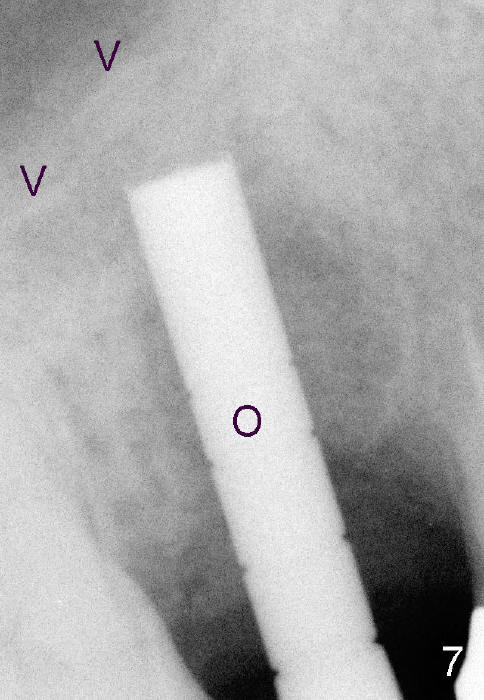

Four months after implant removal, the bony defect appears to increase (Fig.5). Reamers (Fig.6 R)and osteotome (Fig.7 O) are short of the sinus floor (arrowheads). A 5x14 mm tapered implant is placed with primary stability (Fig.8 I). The implant is placed ~ 2 mm deeper (Fig.9). No bone graft is used for sinus lift. There is no complication. The sinus floor appears to be repaired 4.5 months postop (Fig.10). Fig.11 (trimmed from panoramic X-ray) is taken 1 year 7 months post cementation. The bone remains stable 4 years 2 months post cementation (Fig.12); the mesial defect is most likely related to extraction trauma (*).